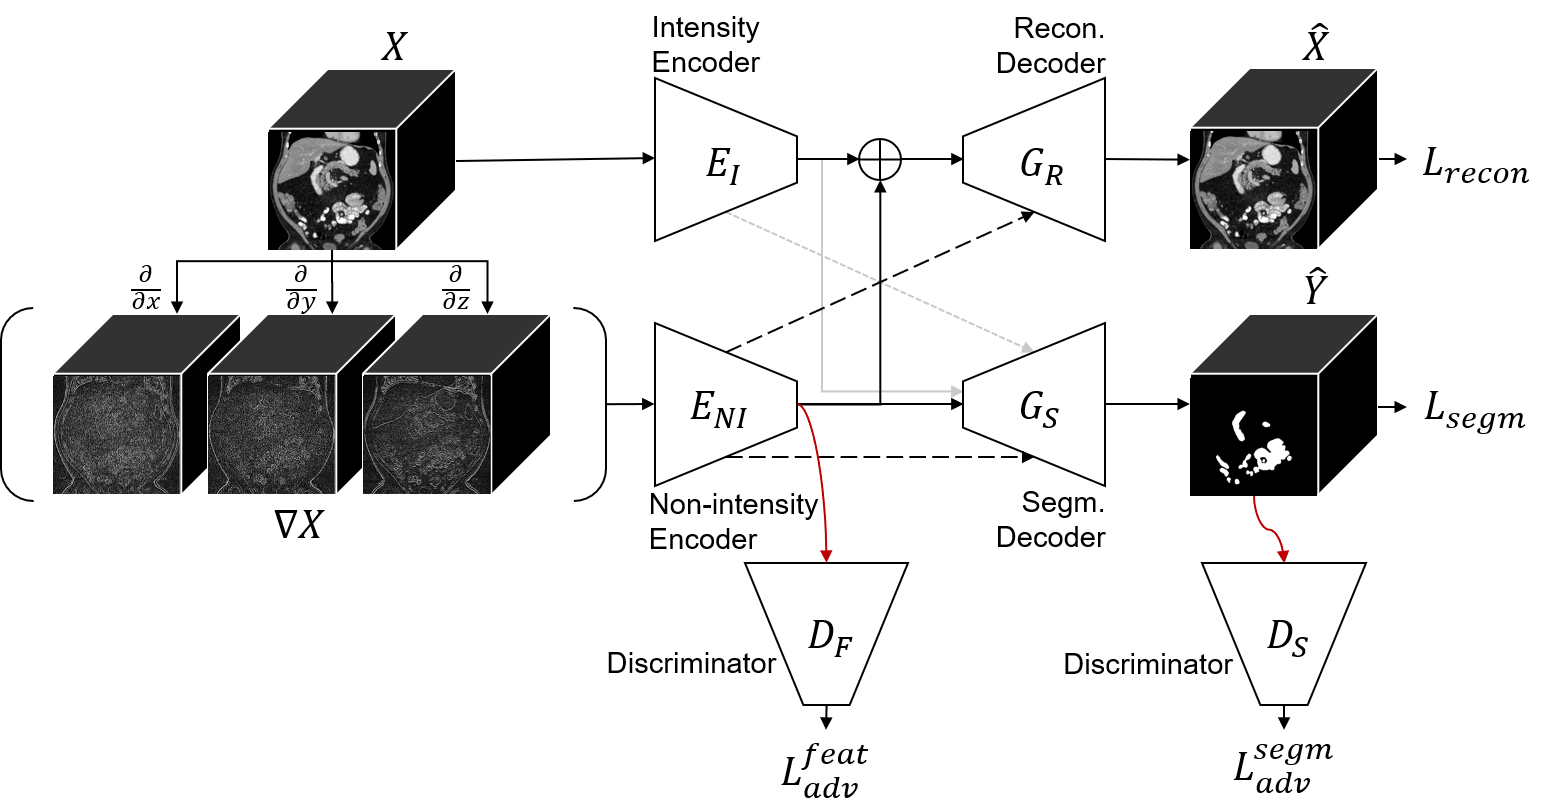

Figure 2 shows the proposed network composed of a sub-network for feature disentanglement and an additional decoder for segmentation prediction based on the disentangled features. The sub-network for feature disentanglement has a two-stream auto-encoding architecture, where the intensity and non-intensity features are first extracted through the separate encoders and , respectively, and then combined in the decoder to reconstruct the input image.

All convolution and pooling layers in the intensity encoder have 1x1x1 kernels to constrain it to see each voxel independently and learn only the intensity information. While the intensity encoder takes the original image as input, the non-intensity encoder uses as input the gradient images of , as shown in Figure 2. As a simple operation, the gradient still maintains the non-intensity information like texture and shape by keeping the relative values of neighboring voxels while losing the absolute values in a CT scan. Thus, the non-intensity encoder is guided to learn the non-intensity features.

The extracted features from both encoders are finally combined to reconstruct the original image in the reconstruction decoder. To prevent this reconstruction from being done solely from the intensity feature, the following are applied: 1) While the lower level features of the non-intensity encoder are used by skip connections, only the innermost features from the intensity encoder are used for reconstruction. 2) Dropout is applied to the intensity features before concatenation with the non-intensity features. We applied the per-element dropout based on empirical evaluation. The loss function for reconstruction is as follows:

2.3 Unsupervised Domain Adaptation using Disentangled Representations

The key idea of this work is to perform the domain adaptation on the disentangled representation, but it is also done in the output level.

2.3.1 Feature Level Adaptation

Adversarial learning is applied to the disentangled non-intensity feature to make it domain-invariant while leaving the intensity feature as it is. The involved fully convolutional discriminator takes the innermost features as input, and outputs , where the value represents the probability that the image is drawn from the source domain for the corresponding position in the feature map. The cross-entropy loss for training is defined as:

| (2) |

where or for the source and target domain images, respectively.

While training the discriminator using images from both domains, an adversarial loss is computed for target domain images . Given the discriminator output , the adversarial loss is defined as:

| (3) |

The non-intensity encoder is encouraged to learn domain-invariant features in order to fool the discriminator during training.

2.3.2 Output Level Adaptation

The segmentation prediction is performed in an additional decoder by aggregating the disentangled features. Being less transferable across domains, the intensity features are optionally used for segmentation prediction, which is implemented by optional connections as shown in Figure 2. The effect of this will be evaluated in section 3. We used the generalized Dice loss [16] for to train the segmentation decoder. The calculation of this supervised loss is possible only for source domain images, meaning that the segmentation decoder is fitted by only source domain images.

To adapt the segmentation decoder, another adversarial learning is applied to the segmentation output . The loss for training the output level discriminator , and the adversarial loss are defined similarly to ones for feature level adaptation but for the segmentation prediction . This encourages the output prediction of the target domain to be similar to the source ones.

2.3.3 Objective Function for Domain Adaptation

Finally, the overall loss function for training the proposed network is:

| (4) | ||||

where , , and are the weight for each loss.